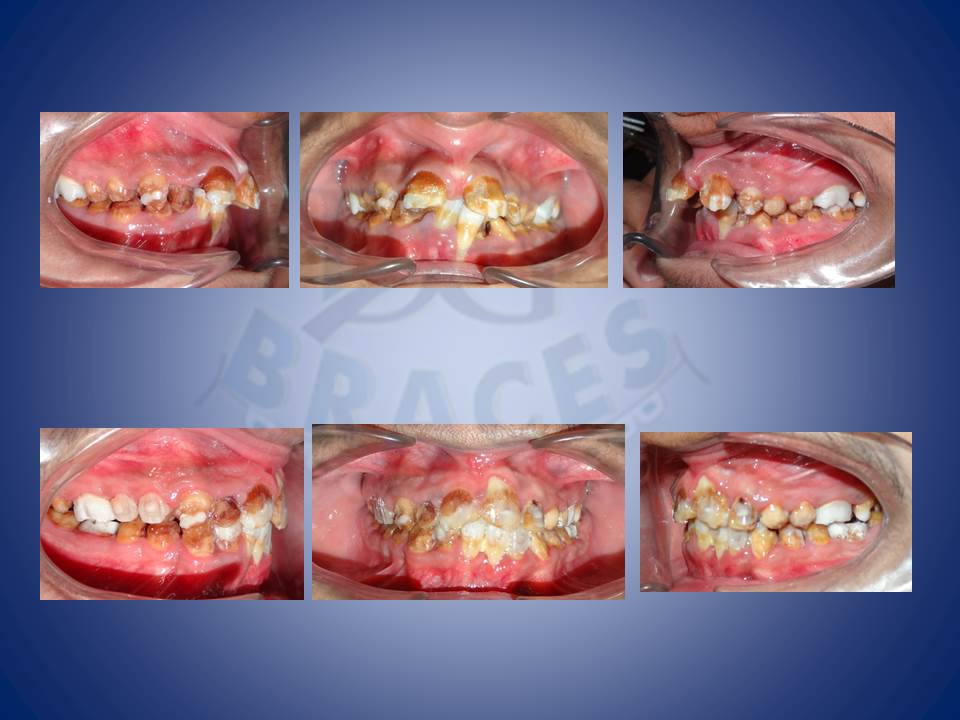

2.Crowding and multiple mutilated teeth are best left treated helping maintainance easy and improving the biting efficiency of patients upto 80%

8.Most times patients will come to Dental office with extra teeth or missing teeth and wanting to replace them with artificial teeth. But why artificial when u can get natural results with a short therapy.

9.An extra tooth usually present in between the centre 2 teeth are often lost mid age and patient is left luring to decide if they need to go for artificial teeth or live with the gap. We say “no to both”. COme to us we shall close them!!!